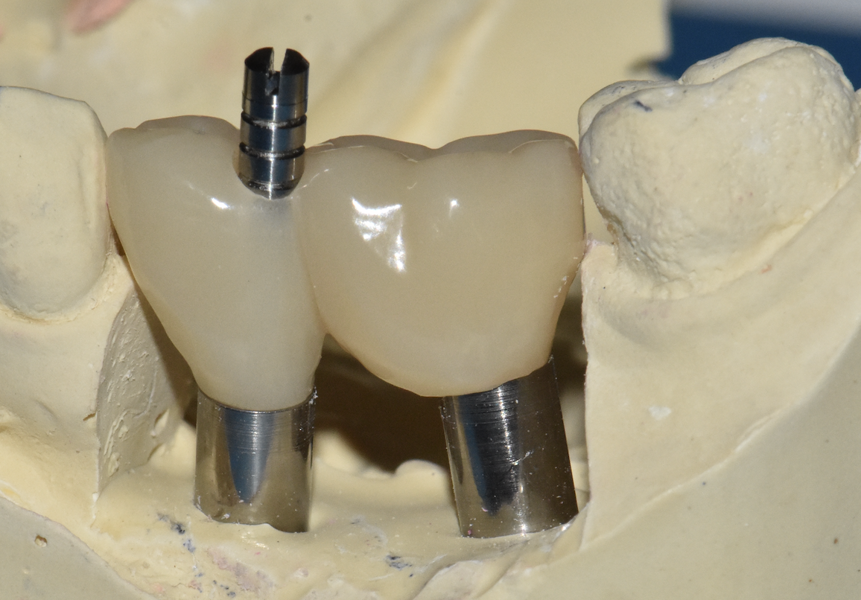

Le Zantex présente donc d’excellentes propriétés de résistance à la traction, de flexion et de compression, tout en ayant une faible densité, pour le confort du patient. Il est biocompatible, facilement réglable, et ne nécessite aucune cuisson, tout en fournissant un haut niveau de liberté de conception et de fabrication. Sa particularité est l’adhésion parfait et durable avec les matériaux utilisés en restauration dentaire. Pour la mise en oeuvre de nos MCI, le Zantex est usiné en armature sur laquelle sont monté des dents du commerce et acrylique, polymérisée en moufle de laboratoire. La rigidité de la contention est donc assurée, et la passivité de la structure obtenue par le collage de cylindres en titane à l’intrados de l’armature (Figs. 4–7).

Un bridge G-CAM a été réalisé en direct implants avec vis sphériques spécialement développées afin de limiter les contraintes au niveau de l’émergence des implants (Figs. 11a–c).